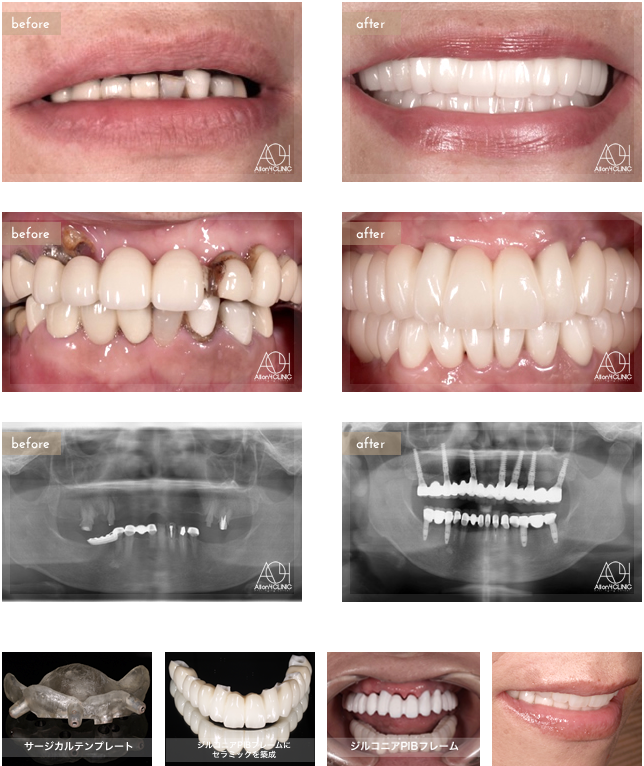

Age : 61

Sex : Female

Treatment :

- Maxilla All-on-4

- Under All-on-4

上顎は7本のNobel Activeインプラントをストレート埋入。上顎上部構造はジルコニアPIBフレームにセラミックを築成。non gumタイプを採用。上下メタルフリーによるフルマウスリコンストラクション。